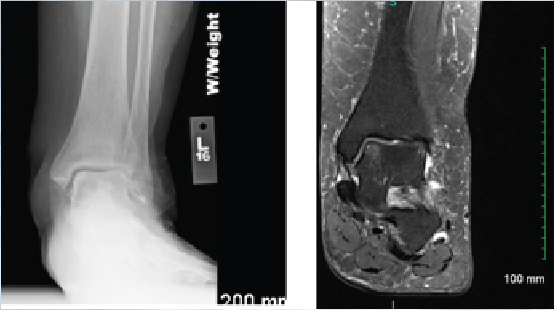

Interestingly, Lee and colleagues looked at the microfracture technique in the presence or absence of subchondral cysts when addressing lesions of the talus.4 They found that microfracture alone produced good outcomes in small to mid-sized lesions regardless of the presence of a cyst. Conversely, the cartilage may remain intact but the underlying flooring has developed cystic changes. In these cases, one may address only the cyst with preservation of the joint surface. Medial talar dome lesions are quite amenable to this through a retrograde technique. In this case presentation, radiographic and magnetic resonance image (MRI) studies suggest intact overlying cartilage with underlying bone marrow edema and early erosive changes.4

In this approach as described by Hyer and colleagues, the authors reviewed eight consecutive patients with a mean follow-up of 24 months.5 They found short-term outcomes comparable to previously described techniques for retrograde drilling of these posteromedial lesions.